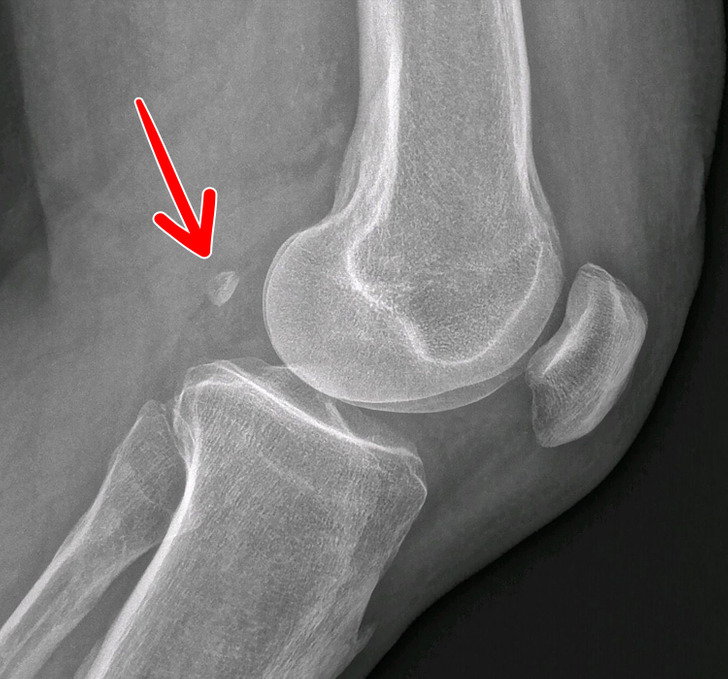

۹- تنها ۳۹ درصد از مردم دنیا یک استخوان اضافه در زانوی خود دارند

این استخوان نه تنها بی فایده است و کاربردی ندارد، بلکه باعث ابتلا به آرتروز هم می شود. به این استخوان لوبیاچه یا فابلا (Fabella) گفته می شود و وجود آن هیچ دلیل تکاملی ای ندارد. این استخوان در تاندونی وجود دارد که عضله را به استخوان ران متصل می کند. اعتقاد بر این است که این استخوان یک نیروی نابرابر به زانوها وارد و احتمال وارد شدن آسیب به غضروف را بیشتر می کند.